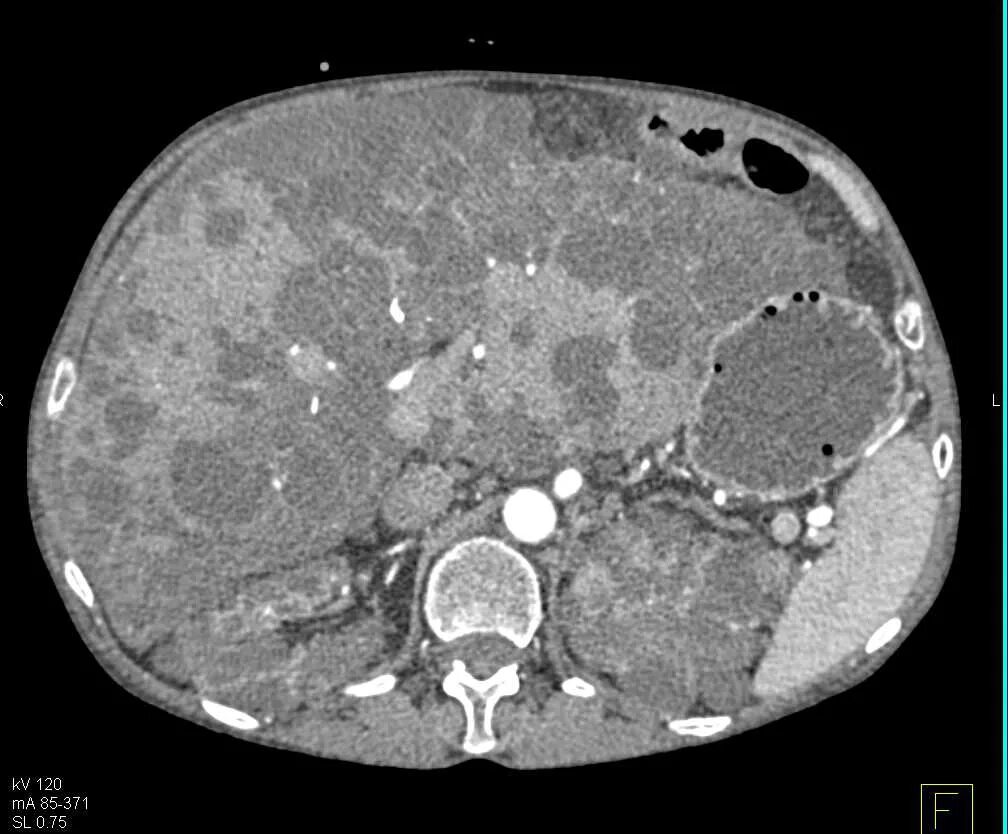

Диффузные изменения паренхимы по типу стеатоза